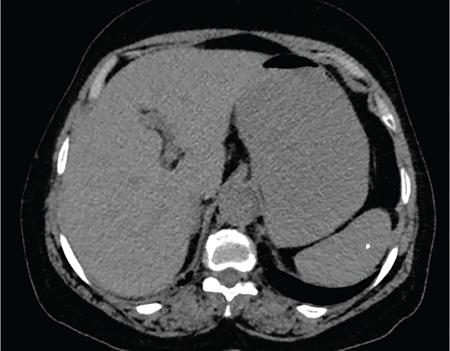

Vijay Kumar K.R. CONGENITAL SPLENIC ABNORMALITIES A multitude of variants and pathologies affect the spleen and it is pertinent for a radiologist to be aware of the common imaging appearances of the same. The spleen begins to develop in the fifth week of gestation from a mass of mesenchymal cells that condense between the two leaves of the dorsal mesogastrium. Several such aggregates fuse to form the lobulated embryonic spleen. The spleen is translocated to the upper left side of the abdominal cavity due to rotation of the stomach and differential growth of the dorsal mesogastrium. The mesogastrium fuses with the peritoneum over the left kidney and forms the splenorenal ligament. The lienorenal ligament fuses dorsally and the splenic artery courses behind the peritoneum as it enters the splenorenal ligament. The portion of dorsal mesentery between the stomach and spleen forms gastrosplenic ligament. Differentiated mesenchymal cells form the parenchyma, connective tissue and capsule of the spleen. The foetal spleen shows lobulations, which normally disappear before birth. However, they may persist along the medial part of the spleen. Sometimes a persisting portion of the spleen may extend medially and anteriorly over the upper pole of the left kidney. It may be mistaken for a space-occupying lesion arising from the kidney. Rarely it may extend posterior to the upper pole of the left kidney, displacing it anteriorly (Fig. 9.22.1.1). The notches and clefts along the superior borders are vestiges of the grooves that initially separated the foetal lobules. They may be 2–3 cm deep. They may mimic a splenic laceration in a patient with abdominal trauma, and the embedded peritoneum at the waist may simulate splenic infarction or haematoma. Hence caution should be exercised. A normal spleen which does not have a fixed ligamentous attachment can change position within the abdomen and is hence known as a wandering spleen. The spleen is normally anchored by the gastrosplenic and lienorenal ligament. Absence or weakness of one or more ligaments that affix the spleen. The spleen with its vascular pedicle as the sole attachment can become a hypermobile intraperitoneal organ. Rarely, the spleen may be normal in position with a wandering accessory spleen. Pregnancy (due to hormonal effects), prune belly syndrome, splenic cysts, malaria, Hodgkin’s disease and lymphangioma. Some of the affected patients may be asymptomatic and diagnosis may be incidental. Clinically it presents as a mobile, palpable, notched mass. Pressure on the vascular pedicle or torsion causes symptoms such as acute abdominal pain, nausea and vomiting. Torsion involving the tail of the pancreas may present as pancreatitis. Confirms the absence of spleen in the left upper quadrant of abdomen with identification of splenic tissue at an ectopic site. Power Doppler, colour Doppler and duplex sonography allow for the identification of blood flow in the splenic vessels and parenchyma. Intermittent torsion may be responsible for an enlarged spleen. Pathognomonic feature of wandering spleen is absence of the spleen in the upper abdominal cavity and presence of a well-demarcated, homogeneously enhancing mass of soft tissue in the pelvis or abdomen. Sometimes a wandering accessory spleen can be visualized as a long vascular pedicle connecting a small mass to the splenic vessels (‘jokari sign’). It can locate ectopic splenic tissue and can also indicate the viability of the tissue. Splenic vessel anatomy can be well demonstrated. 99mTc-sulphur colloid scintigraphy and heat denatured 99mTc-labelled red blood cell imaging provide useful information regarding size and location of splenic tissue. Torsion is indicated by lack of tracer activity in a previously demonstrated wandering spleen. Twisting and torsion of splenic artery can be demonstrated by celiac arteriography. The venous phase may demonstrate splenic vein obstruction with collateral circulation and varices. A congenital focus of normal splenic tissue that is separate from the main body of the spleen is known as an accessory spleen. It results from the failure of fusion of some embryonic splenic buds within the dorsal mesogastrium. Its incidence varies from 10% to 30% on autopsy examinations. They vary from a few millimetres to several centimetres in diameter. They most commonly are found around the splenic hilum. The second most common location is the pancreatic tail. They can also be found in the stomach wall, omentum, mesentery, large bowel and scrotum. Reveals a round or oval mass of tissue around the splenic hilum that is isoechoic with the main spleen. On noncontrast images they are isodense to the main spleen. CECT reveals serpiginous enhancement on arterial phase followed by homogeneous enhancement on venous phase-like spleen (Fig. 9.22.1.2). Accessory spleen is mildly hypointense to the spleen on T1 images and isointense on T2 images. Contrast administration reveals enhancement similar to that of spleen on the arterial, portal and late phases. It is isointense to spleen on DWI images with similar ADC values. 99mTc-sulphur colloid scintigraphy and heat denatured 99mTc-labelled red blood cell imaging show functional uptake in splenic tissue and differentiate splenule from other masses. PET CT-FDG avid mass can mimic tumour. Surgical resection is the preferred mode of treatment in the background of hypersplenism or lymphoma. It is characterized by an ectopic splenic tissue or an abnormal connection between the gonad and the spleen. The left side is more commonly involved than the right side. The accepted theory is that splenic gonadal fusion occurs due to abnormal attachment of the splenic anlage in the left dorsal mesogastrium with the left urogenital fold, during the fifth to eighth weeks of gestation. It has a higher male preponderance and can interfere with left testicular descent and closure of processus vaginalis. It commonly presents as inguinal hernia and cryptorchidism. The spleen and gonad are attached by a fibrous or splenic cord across the peritoneal cavity. It is associated with limb defect syndrome, cleft palate, micrognathia, anal anomalies, craniosynostosis, spina bifida, cardiac malformations, thoracic malformations and diaphragmatic hernias. This is not associated with congenital anomalies. Shows a well-defined scrotal mass with echotexture similar to that of spleen. Confirms splenic tissue in inguinal or scrotal area. It is characterized by the absence of spleen with duplication of right-sided structures. (Right isomerism). It has a slight male preponderance with an incidence of 1 in 40,000 live births. It has a poor prognosis due to its high association with congenital cardiac abnormalities (Fig. 9.22.1.3). It is of uncertain aetiology, and maybe associated with the mutations of CFC1 gene, SHROOM3 gene etc. Delayed development of embryonic curvature can be another cause. It is also theorized that it can be caused due to vascular compromise by pressure on splenic blood supply from adjacent structures. Splenectomy – Usually has a surgical history and is not accompanied by associated anomalies. It is a heterotaxy syndrome associated with multiple spleens and duplication of left-sided structures. (Left isomerism). It has an equal gender predilection with a slightly higher female preponderance. It has a fairly better prognosis than asplenia and is associated with a lesser incidence of cardiovascular anomalies (Fig. 9.22.1.4). It is of uncertain aetiology, and maybe associated with the mutations of CFC1 gene, SHROOM3 gene etc. Accelerated development of embryonic curvature can be another cause. SPLENIC INFECTION AND ABSCESS The infection of the spleen can show three patterns. Fungal and granulomatous infections usually present with multiple micronodules. A pyogenic abscess usually manifest as a solitary lesion. Imaging of diseases causing splenic nodules is never the sole basis for diagnosis. The clinical presentation and laboratory testing (tumour markers, tuberculosis testing and bone marrow biopsy) help in establishing an accurate diagnosis. The imaging findings are nonspecific and the nodules may vary in size from a few millimetres up to 2 cm in diameter. They maybe hypoechoic on ultrasound and hypoattenuating on CT. They are of low signal intensity on T1-weighted sequences and vary from hypointense to hyperintense on the T2-weighted sequences. The nodules show no enhancement or show ring enhancement after contrast study. Healed granulomas are seen as scattered, discrete, small calcifications in an otherwise normal spleen. With increasing number of immunocompromised patients, such as oncology patients undergoing aggressive chemotherapy, critically ill patients in intensive care units, injection drug abusers, and HIV-infected patients, there is rise in the incidence of splenic abscess. For splenic abscess to develop, it may require the presence of bacteremia (sepsis and septic emboli) and altered splenic architecture, which is caused secondary to a haematoma, infarct, or sickle cell disease. Abscesses can also develop from the extension of infection from adjacent organs, like in cases of infected pancreatitis and perinephric abscess, which are less common. In about 20% of cases, cause or source could not be discovered. Abscesses can be unilocular or multilocular, solitary or multiple, depending on the causative organisms and patient’s immunity. Mortality ranges from 15% in otherwise healthy patients with unilocular splenic abscess to 80% in immunocompromised patients with multiple abscesses. Abscesses which are multilocular, gas-containing or due to gram-negative bacillus show poor prognosis. A pyogenic abscess is usually solitary, unilocular/multilocular, but it can also be multifocal. These are uncommon and are reported in 0.14%–0.70% of large autopsy series. Most common presentation is fever (92%), left upper abdominal pain (77%) and leucocytosis (66%). Other symptoms are left pleural effusion and splenomegaly. It can be solitary or multiple, unilocular or multilocular. The appearance of splenic abscess depends on the stage of development. In the early stages of the disease, an abscess appears as an ill-defined mass later developing into a complex collection with septations, debris and sometimes gas. In later stages, after a capsule is developed, the lesion becomes well defined. Left pleural effusion is seen in around 42% of cases. Left lung base atelectasis in 20% of cases and splenomegaly is seen. Abscess with air can be identified based on the presence of extraluminal gas or air–fluid levels in the left upper quadrant. Ultrasonography has a sensitivity of 75%–98% in detecting splenic abscess. This is a very useful modality in patients who are bedridden, with renal impairment and for assessment of small splenic lesions (Fig. 9.22.2.1). Ill-defined hypoechoic mass mimicking a mass is seen in the early phase of the infection and a complex mass with internal septations, debris, rarely acoustic shadowing caused by gas is seen in later stages. The capsule appears as a thin hyperechoic rim. It is noninvasive, speedy, and a modality with high sensitivity (92%–98%). It helps in differentiating unilocular from multilocular lesions and, gives exact anatomical localization and information about perisplenic area, which later helps in planning-guided management procedures. An abscess is seen as a hypodense collection or complex cystic lesion with enhancing rim on the postcontrast study (Fig. 9.22.2.2). CT may help in identifying concurrent areas of infection and, thus, the source of infection. On CT, an abscess may look similar to an infarct, haematoma, or neoplasm. An infarct lacks mass effect, unlike abscess or tumour (Fig. 9.22.2.3). The presence of gas within the lesion is diagnostic of abscess; however, this finding is rare. Splenic abscesses show low signal on T1-weighted images and high signal on T2-weighted images compared with the normal spleen. Minimal to intense peripheral enhancement is seen after IV administration of gadolinium. But MRI is not routinely done, as many patients are clinically unstable. This plays a limited role in the detection and localization of splenic abscess. A nonspecific filling defect is seen on a 99mTc-sulphur colloid scan within spleen if the size is more than 2 cm in diameter. Normal inherent splenic activity on 67Ga scans and 111In-labelled leukocytes scans obscures any kind of inflammatory focus in the spleen, giving rise to false-negative examination. 67Ga scans are nonspecific as tracer uptake can be seen in neoplastic conditions such as lymphoma. Detection and characterization of the abscess are better done if 99mTc-sulphur colloid scan is done prior to 111In-labelled leukocytes scan. FDG PET/CT can also detect the site of infection but not used in the diagnosis of splenic abscess. Early diagnosis of an abscess is prompted for a better outcome. Based on laboratory findings, appropriate antibiotic therapy initiated. USG or CT-guided percutaneous aspiration is tried if the abscess is less than 5 cm in size, and for larger abscesses, percutaneous drainage procedures are done preserving the spleen. Splenectomy is reserved for complicated infections. Fungal abscesses are usually seen in immunocompromised patients with neutropenia such as patients with acquired immunodeficiency syndrome (AIDS), on chemotherapy and immune suppressive agents, and with lymphoproliferative disorders. With the advent of aggressive chemotherapy, the incidence of splenic fungal infections has increased. Approximately 7% of patients with acute leukaemia have hepatosplenic fungal infections. Multiple microabscesses are common. Hepatosplenic candidiasis lesions are very small, and before the advent of CT and MRI, their detection was too difficult. They measure in the range of 5–10 mm in diameter; however, they may be even miliary (<5 mm). Infections are mostly caused by candida species. Other organisms are aspergillus, Histoplasma and Cryptococcus. Imaging characteristics depend on the stage and severity of neutropenia. In cases of chronic disseminated infections with poor neutrophil counts, sometimes lesions are not visible as the host fails to produce an immune response. Lesions become apparent once neutrophil counts improve. Patients presenting with fever and splenomegaly are not improving on conventional antibiotic therapy, and with associated immunocompromised status, fungal infections are to be considered. No single imaging is specific or sensitive in establishing the diagnosis. Serial imaging is needed to detect hepatosplenic involvement; however, tissue diagnosis is the gold standard. Four different patterns are seen in hepatic candidiasis. Multiple, small, homogeneous hypoechoic nodules are the most common finding. Less commonly wheel-within-a-wheel appearance (i.e. the target sign) is seen in the early stage of infection. The first wheel is the peripheral hypoechoic zone of fibrosis and an echogenic second wheel of inflammatory cells around a central hypoechoic nidus containing necrosis and fungal elements. Later these lesions evolve into Bull’s eye lesion where there is a central echogenic focus surrounded by a hypoechoic halo. Lesions become small and hyperechoic with various degrees of posterior acoustic shadowing, with or without calcification, or they may even disappear later in the course of the infection. Splenic nodules are hypodense lesions measuring in the range of 5–10 mm. Only 30% of cases are detected in noncontrast studies. They often have low attenuation, although there can be a focus of high attenuation or a ‘wheel-within-a-wheel’ pattern. Peripheral ring of enhancement is noted in around 70% of cases in the arterial phase of CT, and it is said to disappear on the portal venous phase. There is no significant difference in the detection of the lesions between arterial and portal venous phases of contrast studies. MRI is said to be the investigation of choice for diagnosis of hepatosplenic candidiasis and is superior to CT and USG, especially when short-time inversion recovery sequence is used. MR imaging is also used to monitor the response to antifungal therapy. Based on MRI findings different phases of hepatosplenic candidiasis are described. Lesions are small, measuring less than 1 cm in diameter. They show mildly hypointense on the T1-weighted images and markedly hyperintense on the T2-weighted images. In 2 weeks to 3 months, acute lesions are transformed into subacute lesions. The lesions reveal mildly increased signal on both T1- and T2-weighted sequences. On all sequences, a peripheral ring of very low signal intensity is seen. Following the gadolinium administration, the central region of the lesions show enhancement; however, the peripheral ring continues to have low signal intensity, making them more obvious. It takes from 3 months to more than 1 year for the healed fungal foci composed of fibrous tissue of differing densities and degrees of vascularization to appear on MRI. The lesions measure 1–3 cm, become irregular, and the central area disappears. Chronic healed fungal abscesses have low signal intensity on T1-weighted images and are isointense to mildly hyperintense on T2-weighted images. No perilesional dark ring is noted. These lesions are moderately hypointense on early postgadolinium images and minimally hypointense on delayed postgadolinium images. Mycobacterial tuberculosis infections are mainly seen in immunocompromised patients. Spleen involvement is seen in disseminated, miliary infection in about 80%–100% of autopsy cases; however, it is documented less on imaging. Splenic tuberculosis is seen in the form of nodules measuring ∼ 0.2 and 1 cm in diameter. The macronodular form is very rare (Fig. 9.22.2.4). Hypoechoic pattern is seen. Hypoattenuating nodules with lymphadenopathy noted. Depending on the different stages of the tubercular process, intensities on T1- and T2-weighted images vary. On contrast-enhanced T1-weighted images, lesions most often show peripheral enhancement less commonly gradual peripheral enhancement with complete filling is noted. It is also called as Mycobacterium intracellulare infections. These are also typically seen in immunocompromised patients. Splenomegaly with multiple, low attenuation nodules is seen. Associated findings such as hepatosplenomegaly, diffuse jejunal wall thickening and enlarged lymph nodes are seen. Lymph nodal involvement is homogeneous as opposed to Mycobacterium tuberculosis infections. Focal splenic or hepatic lesions are noted in about 30% of patients with HIV who are infected with M. tuberculosis but are rarely noted in those infected with M. avium intracellulare. Marked splenomegaly is more common in M. avium intracellulare than in M. tuberculosis infection. It is a common opportunistic infection in patients with HIV. Extra pulmonary involvement manifested in the form of necrotizing granulomas. Spleen involvement is an incidental finding. When treated the nodules may enlarge and become progressively calcified in a rim like or punctate fashion. Disseminated infection can show punctate calcification in adrenal glands, pleural or peritoneal effusions, that subsequently calcify. Splenomegaly with small hypoechoic lesions with cystic components or tiny, highly reflective, nonshadowing foci or calcified granulomas. The nodules are hypodense. Calcified granulomas are seen in later stages. This is a self-limited disease caused by bartonellae henselae. Hepatosplenic involvement is rare. This disease is to be considered when a patient presents with abdominal pain, fever of unknown origin, and multiple hypodense lesions in the liver and spleen. It is also called as echinococcosis, a disease seen in endemic regions and in patients emigrated from endemic areas. The causative organism is a zoonotic tapeworm echinococcus granulosus. The most commonly involved organs are the liver, lung, peritoneum, kidney, brain, mediastinum and heart. Spleen is rarely primarily involved. Spleen is involved in approximately 2% of cases of abdominal hydatidosis. Spleen involvement is seen in case of an extensive abdominal hydatidosis, like after the rupture of liver hydatid cyst or in cases of systemic dissemination of infection. Larvae of the tapeworm incite an inflammatory response after its entry into the target tissue in the host where it forms a hydatid cysts consisting of three layers. Peri cyst is an outer layer of modified host cells forming a dense and fibrous layer. The middle layer laminated layer and an inner germinal layer made up of daughter cysts, also called as brood capsules. Scolices develop in the brood capsules. The laminated and germinal layer forms the true cyst wall. After the parasites die, the cysts become inactive, may calcify, and undergo fibrosis. Patients present with abdominal pain, splenomegaly and fever. The diagnosis is to be suspected in all patients from endemic areas presenting with a splenic cyst. A World Health Organization Working Group on echinococcosis has a standardized sonographic classification of echinococcal cysts (Table 9.22.2.1). CE, cysticechinococcosis; CL, undifferentiated simple cystic lesions. Radiological appearances depend on the natural aging process of the cyst. Classic imaging characteristics are lost when the cyst becomes secondarily infected. A ring-like or curvilinear calcification noted in the left hypochondriac region. This may represent the calcification of pericyst in later stages of the disease. Ultrasound is an easy and most commonly used for evaluation of a suspected case of abdominal echinococcal disease. It is used for the diagnosis, planning the management and follow-up. Shifting of brood capsules within the cyst causes fine internal echoes, that is ‘The snowflake sign’ (hydatid sand). Detached laminated endocysts may be seen within the cysts, that is ‘The. Waterlily sign’. Mother cysts may be partially /completely filled by daughter cysts. Calcifications with posterior acoustic shadowing are seen in later stages of the disease. CT and MRI are indicated for widespread disease and complications and for planning percutaneous therapy and surgery. Complications of a hydatid cyst include compression of the adjacent structures, cyst rupture, secondary infections, anaphylaxis and fistulization to surrounding structures. A hydatid cyst may be seen as a well-defined, hypoattenuating cystic lesion with fluid-attenuation values and a distinguishable wall. CT is more sensitive for subtle wall calcification. May appear hyperdense because of debris, hydatid sand and inflammatory cells (Fig. 9.22.2.5). In CE 2 cysts, peripherally arranged daughter cysts, completely fill them other cyst. The daughter cysts show lower attenuation than the mother cyst. Type CE 3 lesions are round or oval with occasional calcification and daughter cysts. They usually show high attenuation. Type CE 4 cysts are complex masses. Intravenous contrast administration reveals enhancement of septa and cyst wall. Type CE 5 cysts are complex cystic or solid-looking lesions, and they can be partially or completely calcified. The simple cysts show low signal on the T1-weighted images and markedly hyperintense on the T2-weighted images. The rim sign which is a low signal intensity rim well seen in T2-weighted MRI images is characteristic of hydatid disease. Enhancement of septa and cyst wall is noted after the intravenous administration of gadolinium. On T1- and T2-weighted images, the maternal matrix appears hyperintense relative to the daughter cysts. The collapsed parasitic membranes may show serpent sign or snake sign, which are hypointense on all sequences. Hypointensity on T1- and T2-weighted images are seen in type CE 4 and CE 5 cysts. The imaging findings combined with the clinical, immunologic testing and epidemiologic results, usually provide the correct diagnosis. Seen in cases of tuberculosis, histoplasmosis, less commonly in Pneumocystis jirovecii pneumonia and brucellosis. These are incidental findings usually preceded by hypoattenuating microabscesses. Microabscesses heal with or without preceding regression. More than five calcifications usually represent histoplasmosis, whereas less than five represent tuberculosis. A ring-like calcification is seen in Pneumocystis carinii pneumonia. Any granulomatous infection is more likely to involve other organs such as the liver, kidneys and lymph nodes. Hydatid cysts can show ring-like or curvilinear calcification (Fig. 9.22.2.6). SPLENOMEGALY AND HYPERSPLENISM Splenomegaly is often a nonspecific finding, and there are many causes for splenomegaly. The spleen can grow into large sizes towards right iliac fossa, crossing midline. On average adult spleen measures <11 cm in length,<7 cm wide,<5 cm thick, and weighs approximately 150 g (80–300 g). The size and weight of the spleen decrease with advancing age. Spleen size is significantly influenced by the sex and body height of an individual. Chow et al. assessed 1230 healthy volunteers and found that spleen length and volume were significantly and independently associated with sex, body height and weight. Taller and heavier male individuals have larger and longer spleens. In one study the spleen length in 6% of women, and 26% of men exceeded a strict upper limit of normal of 12 cm. Rosenberg et al. established an upper limit of standard splenic length of 12 cm for girls and 13 cm for boys (≥15 years). Massive splenomegaly is defined as a spleen size greater than 18 cm, is less common and includes haematological disorders and infections (Table 9.22.3.1).